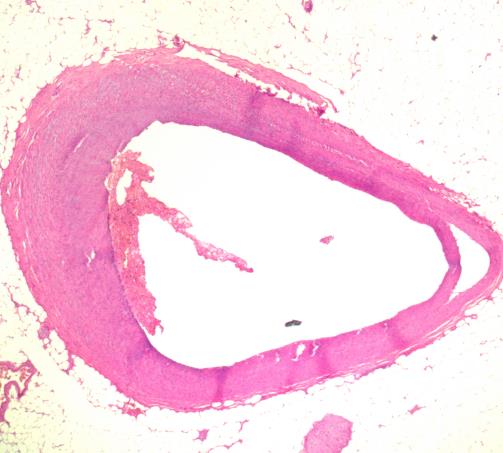

冠脉情况 心肌镜下情况